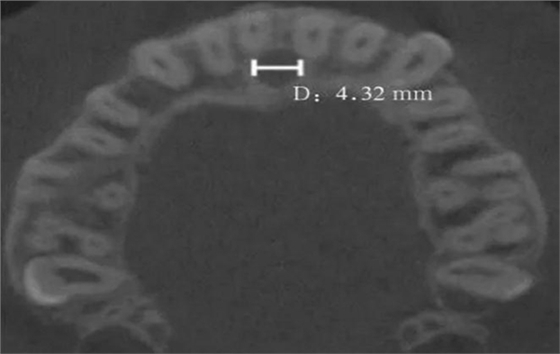

(2)水平面:以第一次觀察到完整的切牙孔形態(tài)的平面作為觀測平面(圖4)。

D:切牙孔橫徑。

圖 4 切牙孔橫徑測量方法

Fig 4 Measurements oftransverse diameter of nasopalatine canal

本研究在可重復的測量方式及較大的樣本量的基礎上進行分析,希望取得更為準確、科學的結果。筆者通過水平面和正中矢狀面對鼻腭管進行評估,得出鼻腭管矢狀面直徑平均值為(3.37±1.58)mm,小于Mraiwa等[5]的測量結果4.6 mm;大于T?züm等[6]的測量結果2.59 mm;與Liang等[3]的測量結果3.4 mm、Thakur等[7]的測量結果3.61 mm和王智等[8]的測量結果3.41 mm相近。鼻腭管平均長度為(13.58±2.22)mm,大于Song等[9]的測量結果12.0 mm;小于AL-Amery等[10]的測量結果16.33 mm;而與Fernández-Alonso等[1]的測量結果(12.34±2.79)mm,以及Zhou等[11]的測量結果(12.80±2.17)mm相近。唇側骨厚度的平均值為(7.63±1.5)mm,與AL-Amery等[10]的測量結果7.54 mm、T?züm等[6]的測量結果(7.17±1.49)mm、Mraiwa等[5]的測量結果(7.4±2.6)mm均相近。在水平面測量中,一些研究[8]對于鼻腭管矢徑和橫徑的長短存在爭議,筆者認為該結果的差異可能是由水平面切牙孔形狀的變異性及對有骨突和不規(guī)則切牙孔測量方法的不確定性造成的。為避免該誤差,本研究只測量切牙孔開口為1個且形狀為圓形的病例,測得水平面鼻腭管直徑為(3.45±0.95)mm,鼻腭管橫徑與矢徑差異無統(tǒng)計學意義。